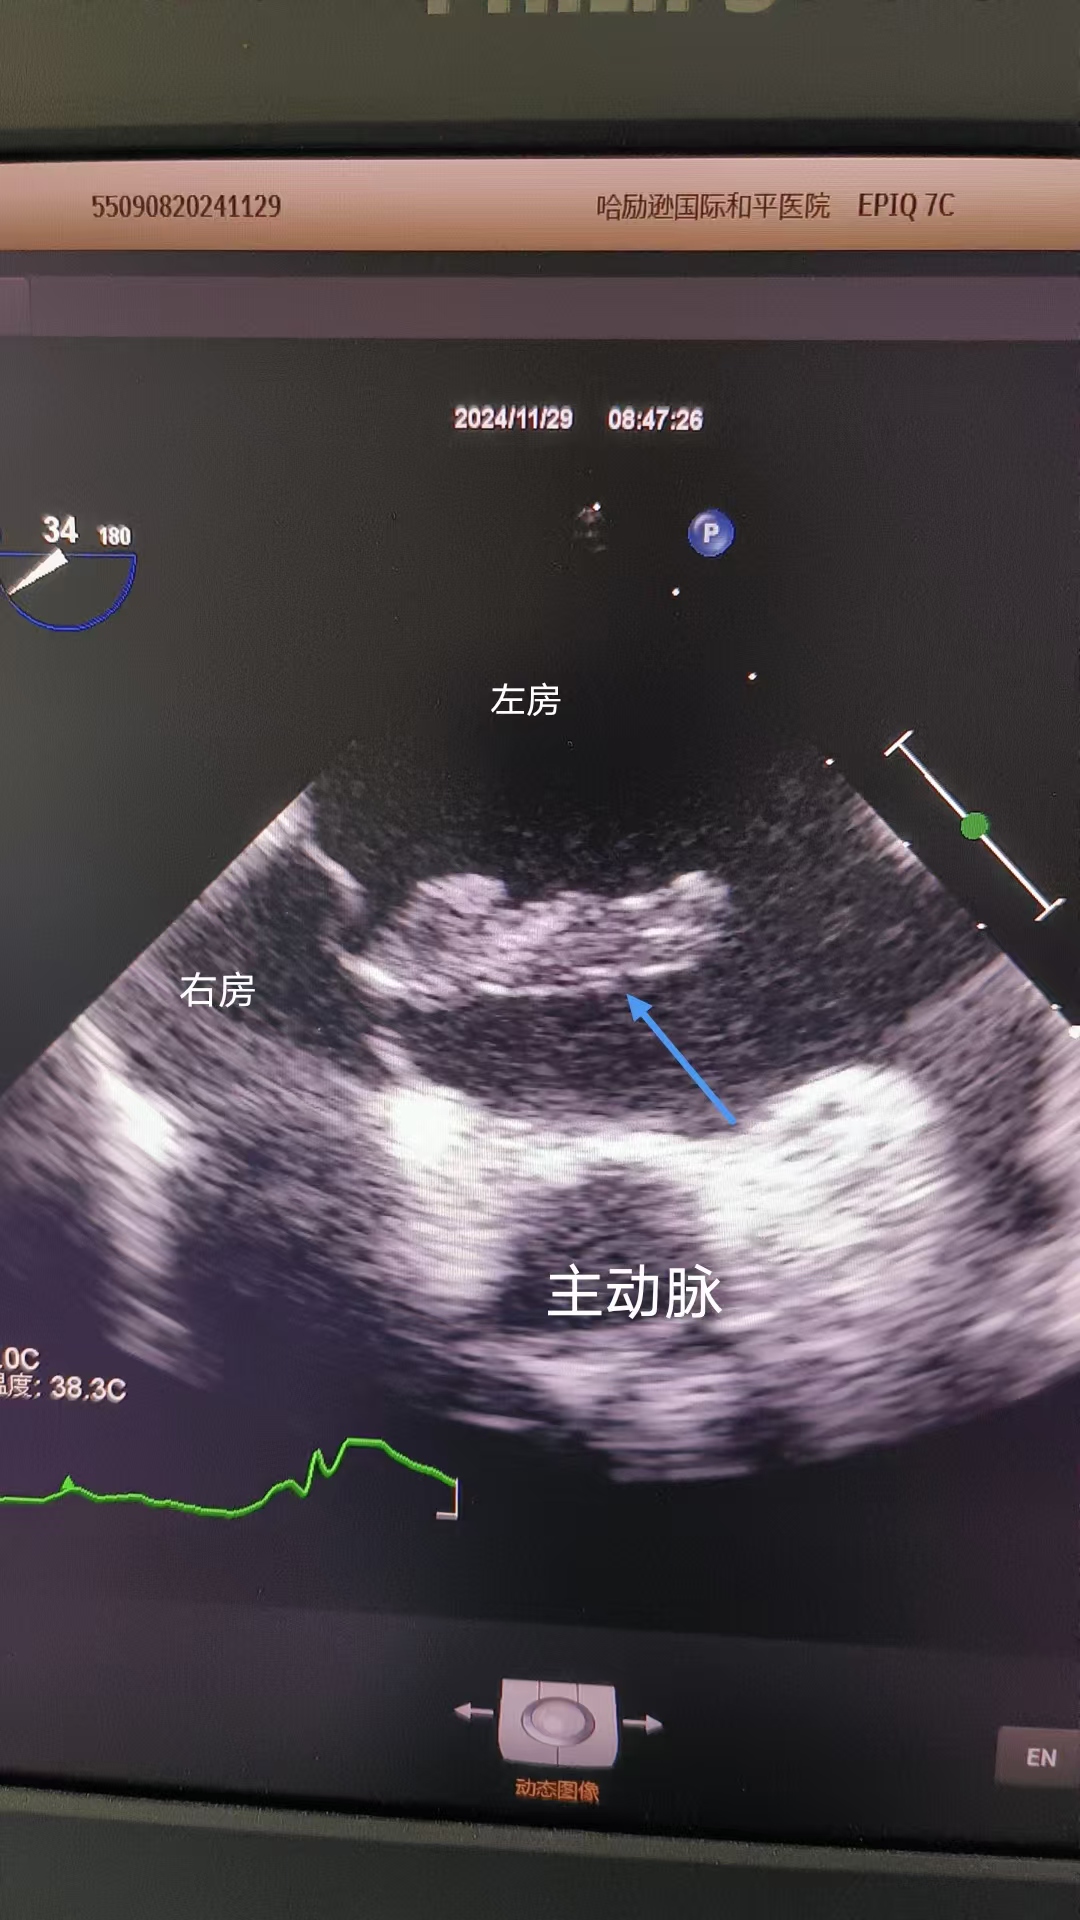

同聲相應(yīng),同氣相求。孫霞、李琳等作為此次無痛經(jīng)食道超聲心動(dòng)圖檢查MDT小組的專家,為此項(xiàng)開先河的檢查提供了堅(jiān)強(qiáng)技術(shù)后盾。姚阿姨的家人了解情況后,也放下心來。在孫霞的指導(dǎo)下,秦麗嫻熟地將直徑僅幾毫米的探頭經(jīng)口腔輕柔、精準(zhǔn)進(jìn)入患者食道,轉(zhuǎn)動(dòng)探頭,從0°到180°的視覺,來檢查心臟的各個(gè)腔室、各瓣膜的情況,對(duì)心臟左房內(nèi)團(tuán)塊進(jìn)行全方位評(píng)估,通過其在左房的位置、活動(dòng)度、回聲、腫物蒂的情況等,最后考慮為左房粘液瘤。檢查結(jié)束后,姚阿姨感慨萬分:“本以為會(huì)很難受,沒想到睡一覺就結(jié)束了,醒來也沒有不舒服,高科技真是神奇!”

高清晰度的無痛經(jīng)食道超聲心動(dòng)圖檢查影像報(bào)告。